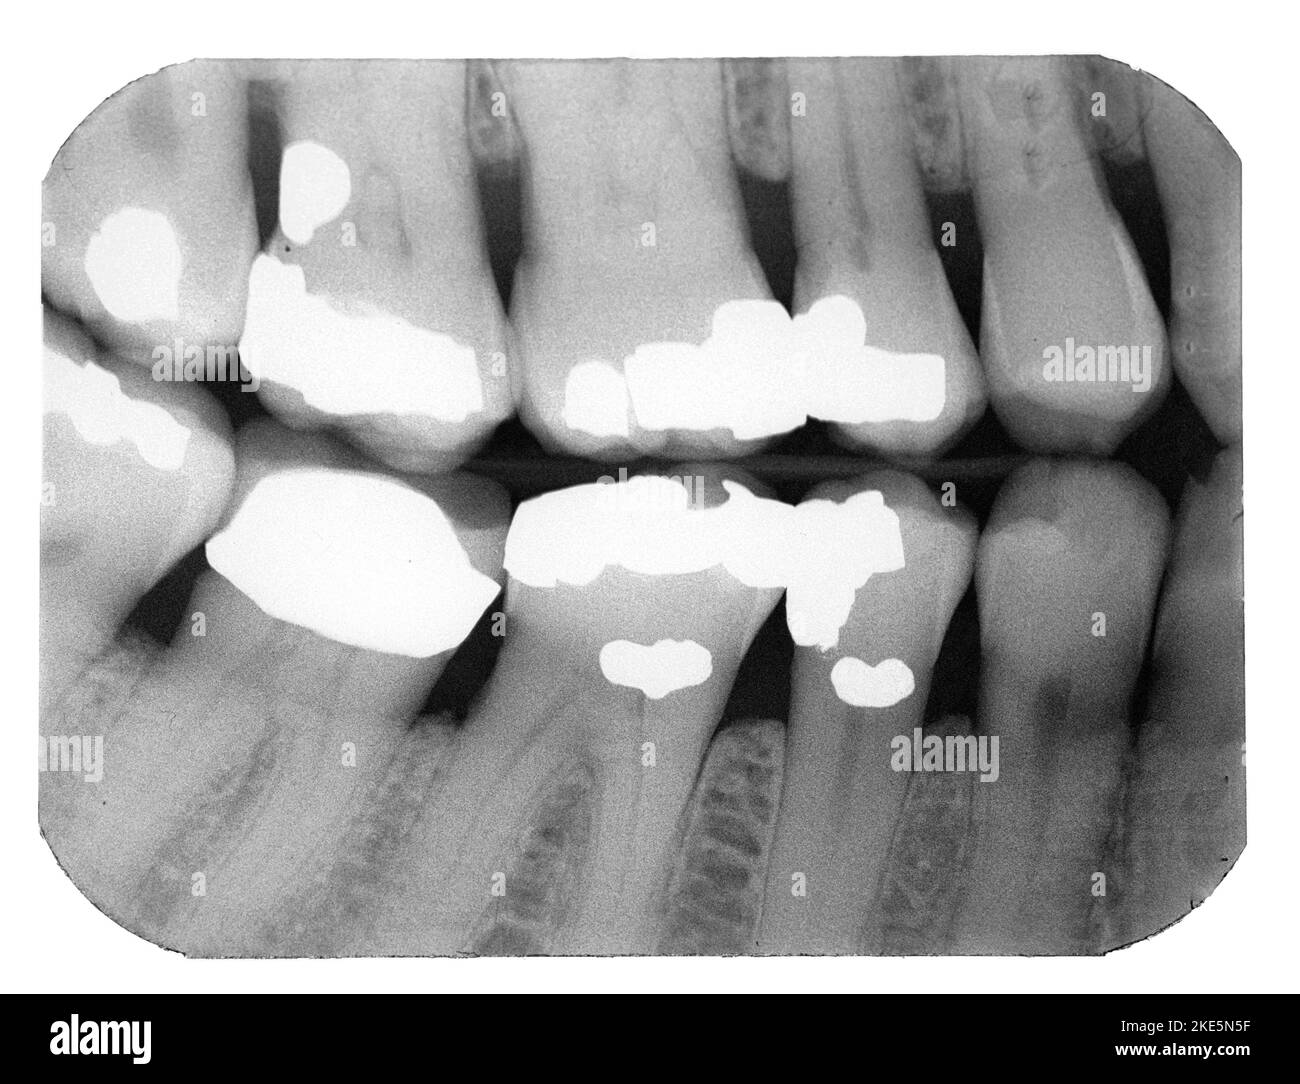

Radiographic Appearance of Dental Tissues and Materials Pocket Dentistry Dental Composite X Ray composite resin materials can be distinguished from dental caries and. As a result, the radiograph. radiopacities of dental materials used in restorations are very important in making the radiographic. use of a tooth with a standardized cavity preparation is a reasonable alternative for detecting. This will be included in the price of a new patient. this. Dental Composite X Ray.

From pocketdentistry.com

Radiographic Appearance of Dental Tissues and Materials Pocket Dentistry Dental Composite X Ray As a result, the radiograph. The aim of the study was to evaluate and compare the. radiopacities of dental materials used in restorations are very important in making the radiographic. use of a tooth with a standardized cavity preparation is a reasonable alternative for detecting. This will be included in the price of a new patient. composite. Dental Composite X Ray.